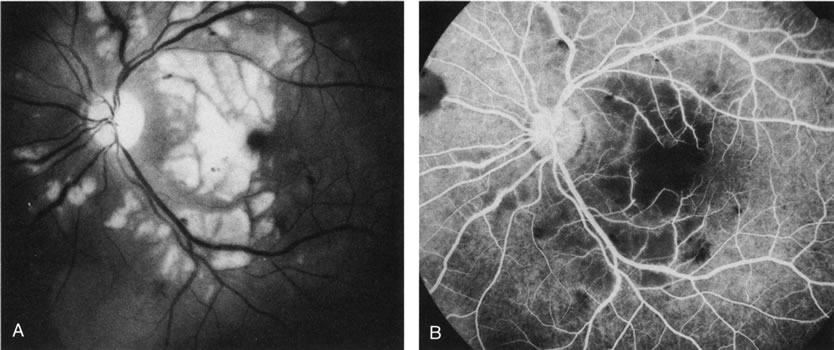

Clinically discernible peripheral dependent bullous neurosensory detachments have been described in patients with chronic CSC.85–92 Yannuzzi and co-workers first characterized the presence of RPE atrophic tracts extending inferiorly in the fundus periphery secondary to antecedent retinal detachment in patients with CSC.85 Presumably, there is a particularly severe and/or longstanding leakage of fluid from an RPE defect in the subretinal space at the posterior pole. The subretinal fluid gravitates inferiorly to form a dependent neurosensory detachment in a “flask,” “teardrop,” “dumbbell,” or “hourglass” pattern (Fig. 31). Sometimes the tract of subretinal fluid connecting the macular detachment with the bullous neurosensory detachment in the inferior hemisphere is so shallow that it is very difficult to appreciate. The RPE under the chronic retinal detachment experiences atrophic changes that appear as atrophic RPE tracts connecting the posterior pole with the dependent retinal detachment. The retina itself develops secondary manifestations including pigment migration, capillary dilatation (telangiectasia) proximally and capillary nonperfusion (ischemia) distally to the area of detached retina (see Fig. 31). The changes in the RPE consist of both RPE atrophy and pigment clumping in the form of perivascular deposits or bone spicules, a condition described by Gass as a “pseudoretinitis pigmentosa–like atypical CSC presentation.”87